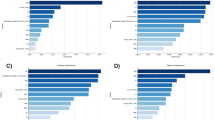

The computer program selected the best seven out of nine measurements in stepwise analysis. Including additional variables fails to substantially improve sex determination. The model with the GM–BaN alone classifies 73% of the sexes correctly. The models with two variables [GM–BaN and basi-bregmatic height (Ba–Br)] and three variables (GM–BaN, Ba–Br, and MaHt) classify the sexes with 84% and 90% accuracy, respectively, whereas the models with four, five, six, and seven cephalometric variables [GM–BaN, Ba–Br, MaHt, foramen magnum length (Ba–O), GPI, IOP–BaN, and frontal sinus width on inner bregma to nasion line (FSWd)] classify the sexes with accuracy ranging from 92% to 95% (Table 4). Using the same variable models, the correct sex determination rate of the resubstitution approach is the same as that in stepwise discriminant analysis (Table 5).

The cross-validation methods (the leave-one-out classification) with one, two, and three variables yield correct sex determination rates of 73%, 84%, and 90%, respectively, as in the stepwise discriminant analysis and resubstitution classification. However, the classification accuracy of cross-validation procedures with four, five, six, and seven variables all produce the same rate of 91% (Table 6).